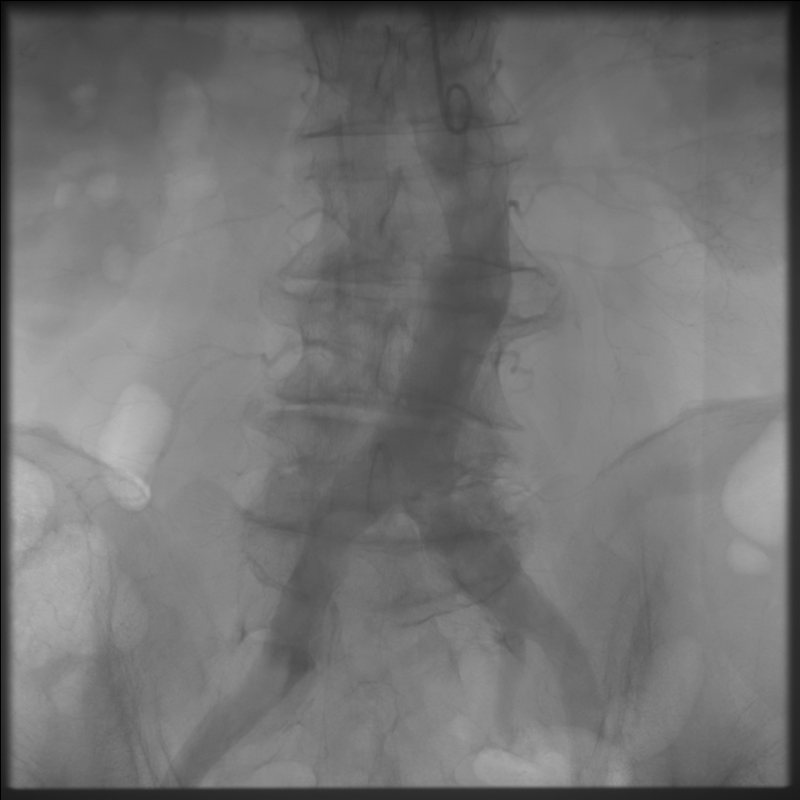

Рентгенэндоваскулярные вмешательства

эндопротезирование брюшной аорты